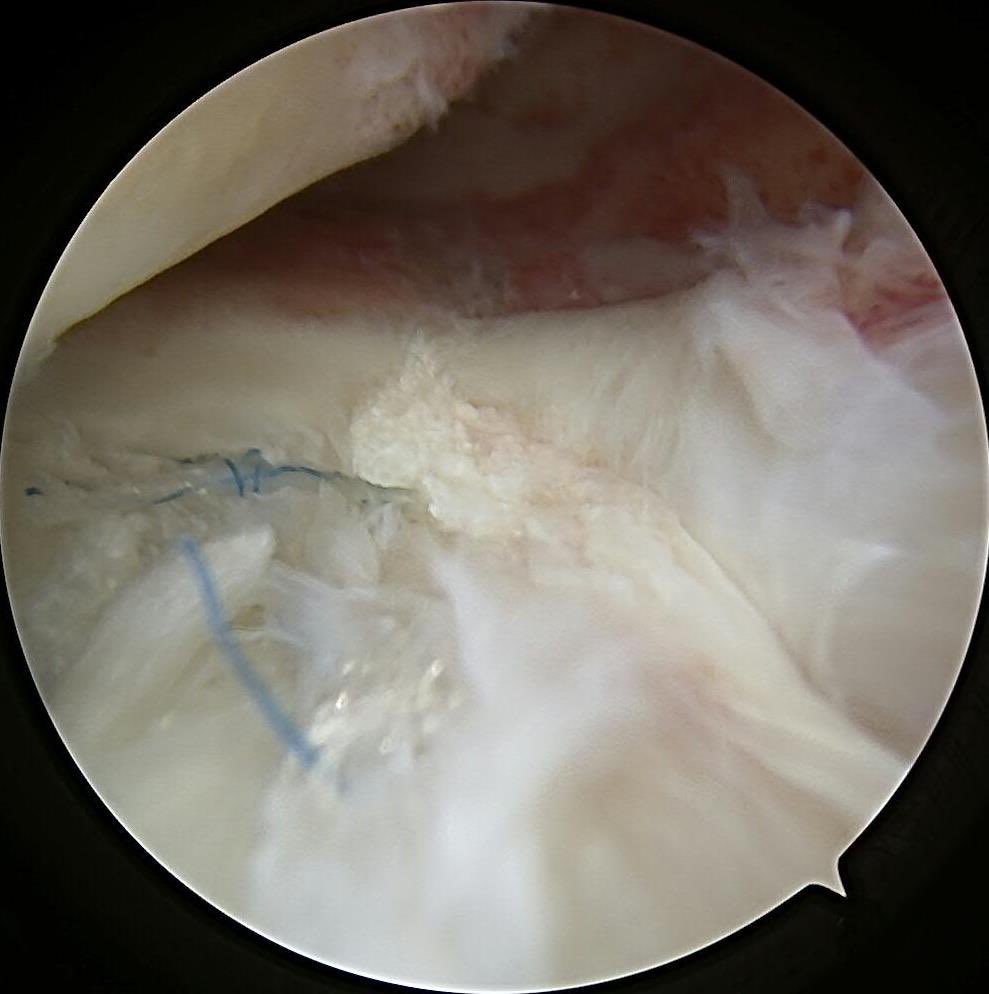

#savethemeniscus LMORT: Lateral Meniscus Oblique Radial Tear- often seen with an acute ACL injury. REPAIR or RESECT?